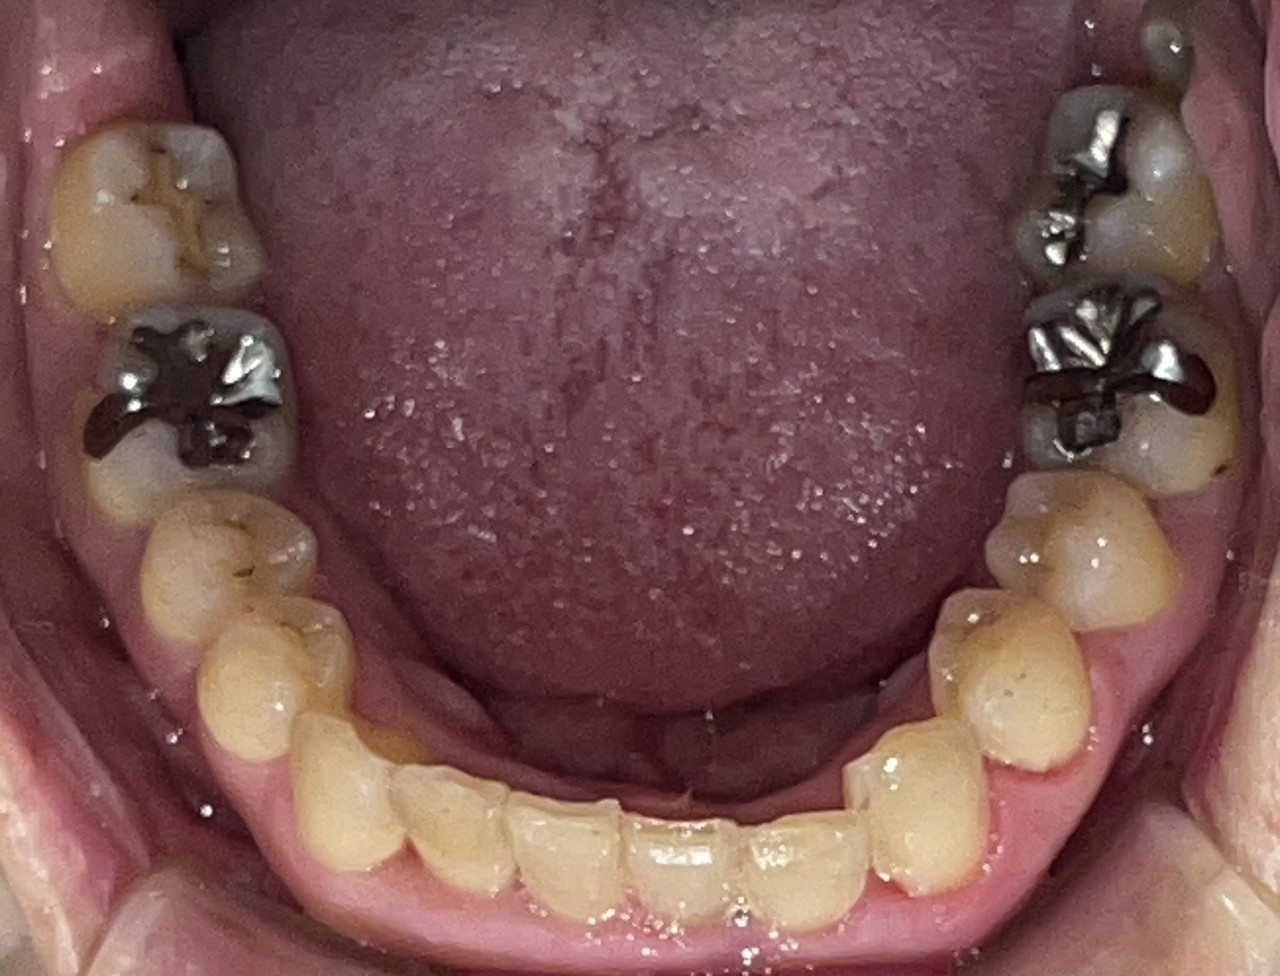

Before

After

矯正の種類 / SmileTRU

年齢・性別 / 30代女性

主訴  /  下顎前歯部の歯並びがガタガタしている(叢生症例)

治療期間 / 8ヶ月

費用 / 模型・3Dデータ診断 35,000円(税別)

上顎マウスピース14枚 308,000円(税別)下顎マウスピース8枚 176,000円(税別)

※マウスピース交換時別途調節料3,000円(税別)

副作用 / 口内炎・歯の移動に伴う痛み・知覚過敏 ※数日で収まる場合が多いです

リスク / 後戻り防止の為、夜のみマウスピースで保定を指示